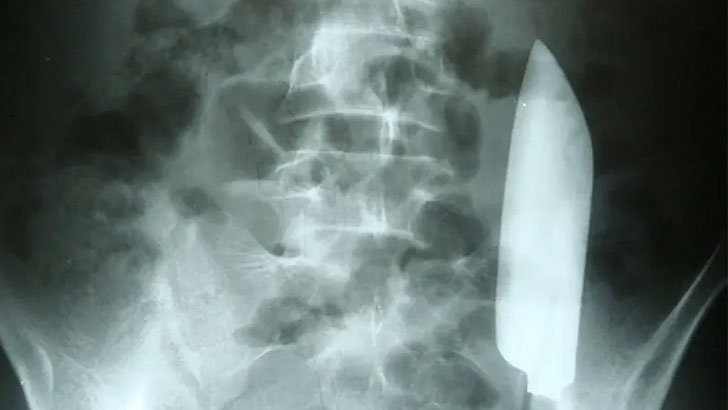

নেপালে ২২ বছর বয়সি এক ব্যক্তি পেটব্যথা নিয়ে হাসপাতালে গিয়েছিলেন। চিকিৎসকরা এক্স-রে করে ওই যুবকের পেটের ভেতরে ১৫ সেন্টিমিটারের ছুরির ফলা খুঁজে পান।

সম্প্রতি বন্ধুদের সঙ্গে মদের আড্ডায় কেউ একজন তার পেটে ছুরি চালিয়ে দেন। তখন হাসপাতালে নেওয়া হলে তার ক্ষতের জায়গায় সেলাই করে দেন স্বাস্থ্যকর্মী। কেউ বুঝতে পারেনি তখনো ছুরির অর্ধেকাংশ রয়ে গেছে যুবকের পেটের ভেতর।

ছুরির ফলাটি অপসারণের জন্য চিকিৎসকরা অস্ত্রোপচার করেন। তাদের ধারণা ওই যুবক সুস্থ হয়ে উঠেছেন। যদিও পরে তিনি আর হাসপাতালে ফেরেননি।